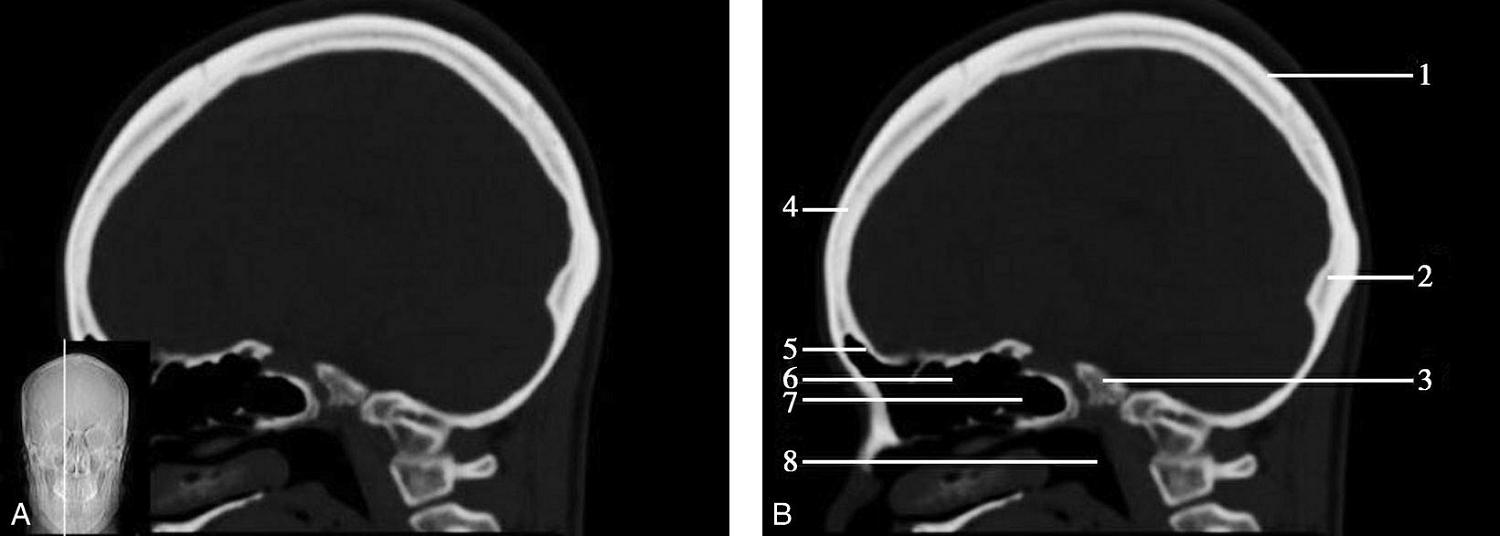

重要结构:胼胝体、垂体、中脑导水管、扣带回、中央沟、第三脑室、斜坡(图1-2-59、图1-2-60)。

图1-2-59 正中矢状面CT

A.矢状面;B.矢状面标注

1.中央沟;2.扣带回;3.胼胝体体部;4.侧脑室;5.中脑;6.胼胝体膝部;7.穹隆;8.第三脑室;9.胼胝体压部;10.垂体;11.中脑导水管;12.第四脑室;13.脑桥;14.蝶窦;15.斜坡;16.小脑扁桃体;17.延髓

图1-2-60 正中矢状面骨窗CT

1.顶骨;2.枕骨;3.斜坡;4.额骨;5.蝶鞍

此层面可显示胼胝体全貌,它位于层面中央区域,是呈上凸下凹的弧形结构,由前向后分为嘴、膝、体和压四部分。扣带回环绕胼胝体上方,扣带沟位于扣带回的上方。大脑半球中部和后部分别可见较深且恒定的中央沟和顶枕沟。中央沟为是额叶顶叶分界标志。